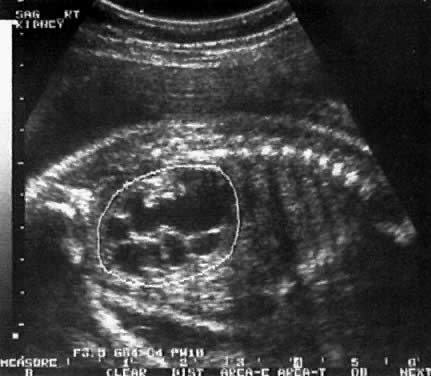

Posterior Urethral Valve

Most PUVs are partial, such that the resulting bladder dilation is not severe. The ureters may only be slightly dilated, and if present, hydronephrosis is moderate (Fig. 13). In the severe form, however, the pathophysiology is severe and may resemble the findings in agenesis of the urethra. In complete PUV, the bladder is markedly dilated. The ureters also are convoluted and large. Hydronephrosis is severe. Oligohydramnios prevents appropriate pulmonary development and leads to pulmonary hypoplasia.

Fig. 13. Longitudinal echogram showing some enlargement of the bladder ( arrow) in a fetus with a partial posterior urethral valve. Ureters are not dilated, and there is no evidence of hydronephrosis.